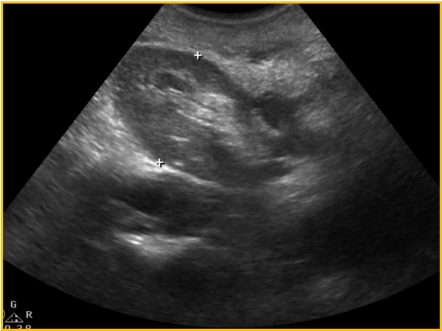

Although there were no other symptoms, a slow increase in serum creatinine, from 1,5mg/dL to 2,4mg/dL, was noticed in the first three post-operative years. Physical examination found a right sided inguinal hernia. Abdominal ultrasound revealed a severe hydronephrosis of the transplant kidney but the ureter could not be visualized. An abdominal computed tomography (CT) showed severe ureterohydronephrosis with herniation of the ureter into the inguinal canal (Figure 1), prompting surgical exploration. Through the previous right-side Gibson incision, the spermatic funiculi and hernial sac were identified and isolated. Exploration of the herniary sac revealed a long ureter, with a dilated proximal portion (3cm wide), followed by an abrupt transition to a rather typical distal segment, close to the bladder wall (Figure 2). Both segments appeared well vascularized and viable. Given these findings and the excessive length of the ureter, ureterectomy of the distal segment followed by a tailored ureteroplasty (Figure 3) and new Lich-Gregoir ureteroneocystostomy of the proximal segment over a double J stent was performed. The posterior wall defect was mended through Lichtenstein technique. A bladder catheter was kept for one week and the ureteral stent for one month. After the removal of the bladder catheter, ultrasound and CT scan were unremarkable (Figure 4) and serum creatinine decreased from 2.4mg/dL to 2.05mg/dL. Patient is still in follow-up, without any sign of recurrence.

Figure 1. CT scan: blue arrow – bladder; yellow arrow – herniated ureter through the inguinal canal

The US mostly reveals severe hydronephrosis and no visualization of ureter´s full length. The CT scan shows the transplanted ureter dilation and the ureteric- inguinal hernia, making it possible to come to the anatomical diagnosis [1,15,18]. There was no explanation for the need of MRI, but one could think that the pelvic area and the inguinal canal anatomical features may become even more striking through these images.